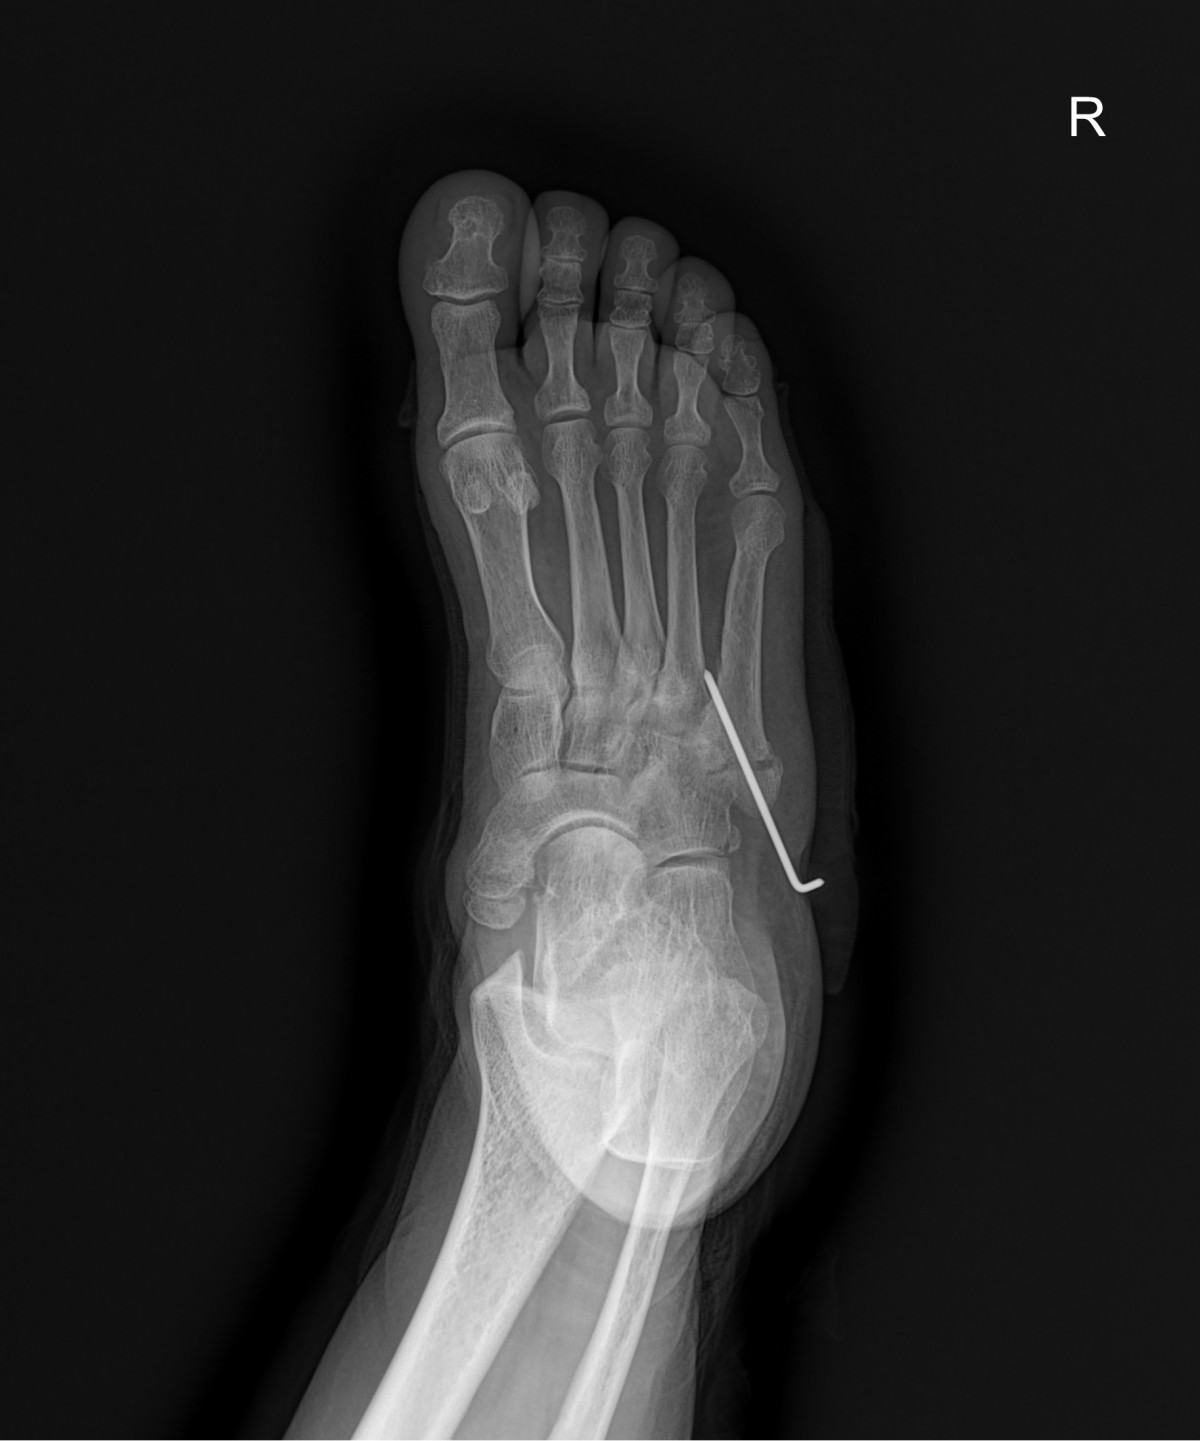

정지영원장님 발등 골절 수술 양순O 환자

dae765e4d9ac96aee867c9d6292d8784_1758008305_2714.jpg